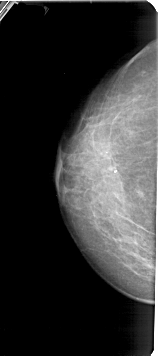

A_1425_1.LEFT_MLO

LEFT_CC LINES 5326 PIXELS_PER_LINE 2356 BITS_PER_PIXEL 12 RESOLUTION 43.5 NON_OVERLAY